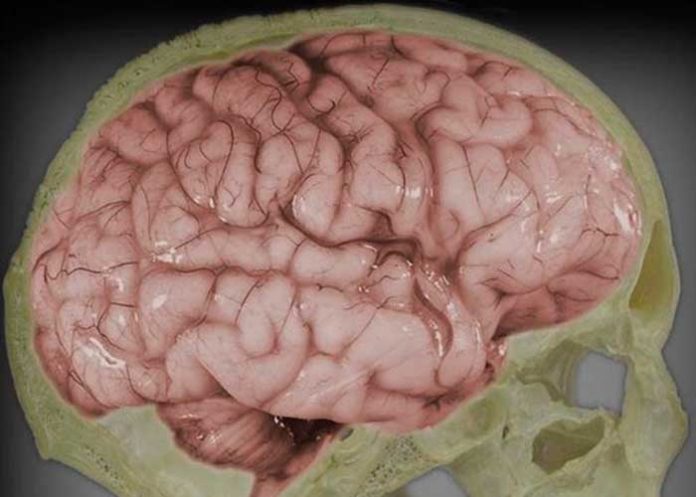

Pero, ahora, un nuevo estudio realizado por un equipo del Hospital General de Massachusetts , ha descubierto la existencia de túneles secretos que conectan la médula ósea del cráneo con el tejido cerebral. El hallazgo fue posible gracias a un experimento con ratones, en el que los investigadores se fijaron en un tipo de células inmunes llamadas neutrófilos, que suelen ser las primeras en llegar al lugar donde se ha producido el daño.

Los investigadores marcaron con fluidos fluorescentes los neutrófilos producidos por la tibia y el cráneo, y observaron que en el caso de un accidente isquémico en el cerebro, los que acudían en respuesta a la inflamación estaban generados en el cráneo.

Y una observación más detallada de la capa interna del cráneo que separa la médula de las meninges, les permitió descubrir la existencia de unos canales totalmente desconocidos hasta ahora, que conectaban el hueso con el tejido cerebral, y a través de los cuales viajaban los neutrófilos. Incluso, en el sentido contrario al del torrente sanguíneo.